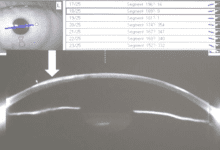

准分子激光角膜屈光手术后,因角膜持续扩张而导致继发性圆锥角膜,是LASIK术后最为严重的并发症之一,可导致最佳矫正视力的丢失,严重者甚至需要进行角膜移植手术。因此,最容易引起医疗投诉与纠纷。 Seiler教授于1998年首次报道LASIK术...